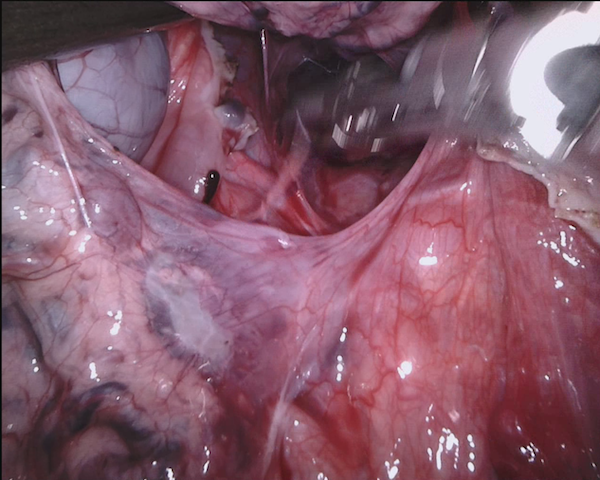

Our challenge was made up of 3 sub-problems. The first was binary instrument segmentation, where each frame was separated into da Vinci Xi instruments and a background class, which contained an ultrasound probe, surgical clips and porcine tissues. The second task was instrument part segmentation, where we scored the participants on whether they could correctly segment each articulating part of the instrument (see Fig. 3). Our final task was to segment and classify the instruments (see Fig. 4).

We provided the first 225 frames of 8 sequences as training data and kept the last 75 frames of those 8 sequences as test data. 2 of the full 300 frame sequences were kept as test sequences. Test labels were kept hidden from the participants. Our datasets contain 7 different robotic surgical instruments. The Large Needle Driver, Prograsp Forceps, Monopolar Curved Scissors, Cadiere Forceps, Bipolar Forceps, Vessel Sealer and additionally a drop-in ultrasound probe, which is typically held in the jaws of the Prograsp Forceps instrument. Samples from the training datasets are depicted in Fig. 2 and examples of the different instrument types are shown in Figure 3 and 4.

IV-D Type Segmentation

The final challenge was to identify each instrument type from the list of Large Needle Driver, Prograsp Forceps, Monopolar Curved Scissors, Vessel Sealer, Fenestrated Bipolar Forceps and Grasping Retractor (see Fig. 4). Only 6 teams participated in this challenge, due particularly to the significant increase in difficulty in recognizing many of the da Vinci instruments from one another.